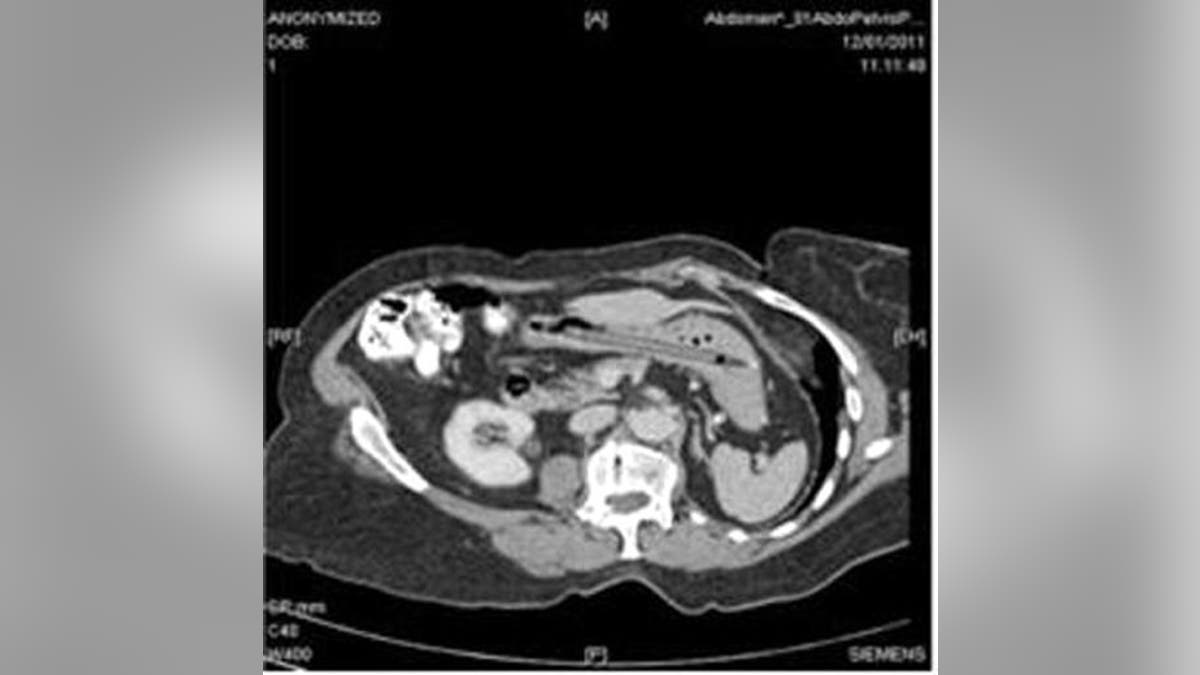

When doctors – and the woman’s husband - didn’t believe her an X-ray proved she was right.